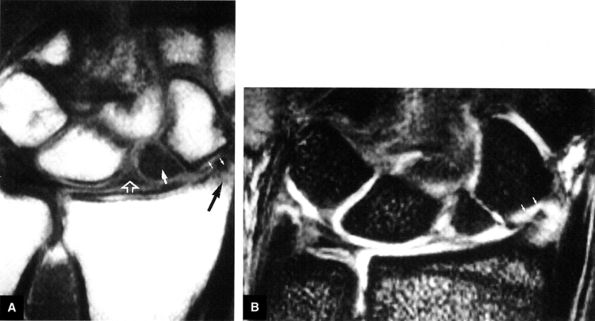

|